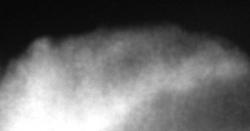

Иллюстрации 6 и 8. Структура акромиального отростка лопатки. Структура неоднородная. Четко определяются два участка остеопороза (деструкция), в медиальных отделах – неоднородный остеосклероз. Нижний контур акромиального отростка неровный, склерозированный. Верхний контур, особенно в верхне-медиальном отделе неровный. Определяется выраженное сужение щели в ключично-акромиальном сочленении.